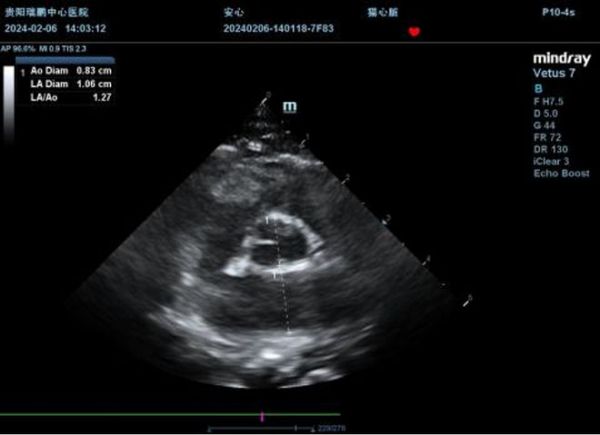

2月6日、2月7号患猫按时用药,病情稳定,呼吸均在50-60次/min之间,浅快,精神良好,小便顺畅,主动进食,主要提供的是鸡胸肉、猫条、全价猫罐头等食物,让患猫自由采食。由于利尿剂的缘故,脱水还在加重,患猫体重从4.4kg下降至4kg,复查心脏超声,可见LA/AO=1.27,左房明显减小,考虑与脱水有关,保持手动喂水,将呋塞米减量至1mg/kg iv bid,其他药物保持不变。

结果提示:LA/AO=1.27,对比2月5号左房明显变小,与利尿后脱水有关。